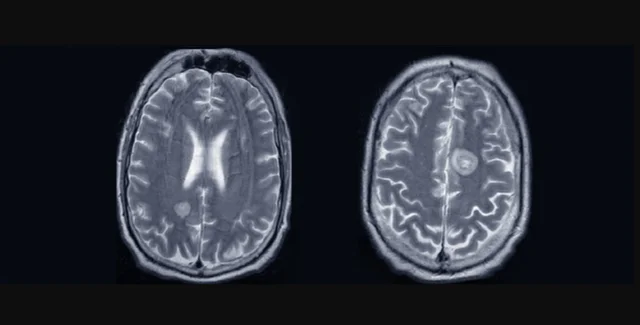

МРТ поражений головного мозга пациента, соответствующих внутричерепным метастазам | Фото: Broderick et al., BMJ Case Report

В отличие от предыдущих сообщений о случаях, у этого пациента изначально не было заметных опухолей в головном мозге, хотя некоторые из них действительно возникали по мере прогрессирования болезни.